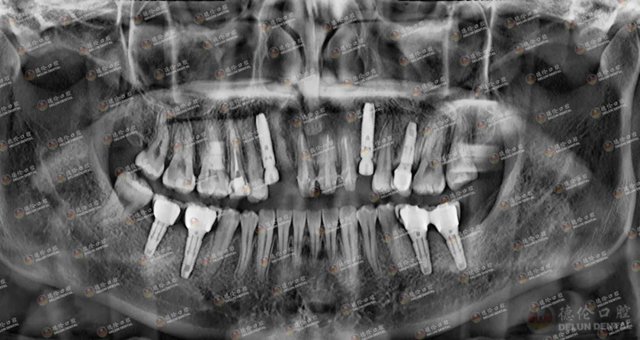

眼见自己的牙齿一天不如一天,2020年5月,刘女士来到德伦口腔区庄旗舰院,寻求崔保亮院长的帮助。经崔院长详细检查,刘女士多颗龋齿龋坏严重,即使做根管治疗也无法保留,只能作拔除处理,后做种植牙。

刘女士术后牙片